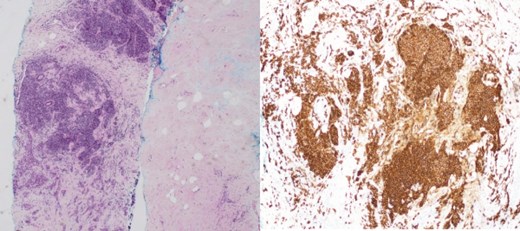

(Left) Breast core biopsy showing periductal atypical lymphoid proliferation. (H&E stain, 20 times magnification); (Right) Breast core biopsy with immunohistochemical staining showing atypical lymphoid cells positive for CD20 stains.

(Left) Breast core biopsy showing follicular hyperplastic nodules of atypical lymphoid cells (H&E stain, 40 times magnification); (Right) Breast core biopsy with immunohistochemical staining; atypical lymphoid cells forming hyperplastic nodules positive for CD20 stains.